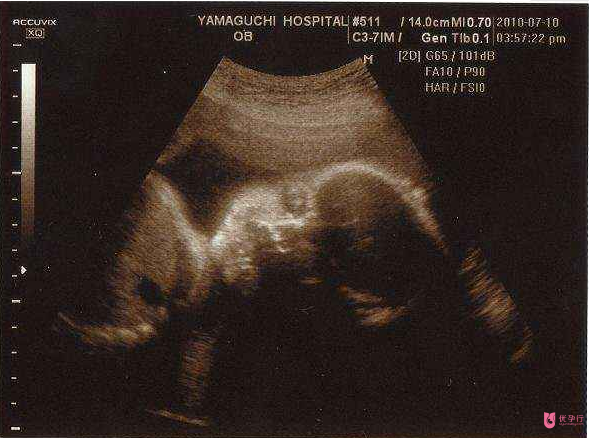

即便成功懷孕,宋女士也不敢有任何松懈,生怕再次流產(chǎn),孕42天,宋女士孕檢胎心正常,寶寶發(fā)育良好,目前宋女士已經(jīng)在家待產(chǎn)。